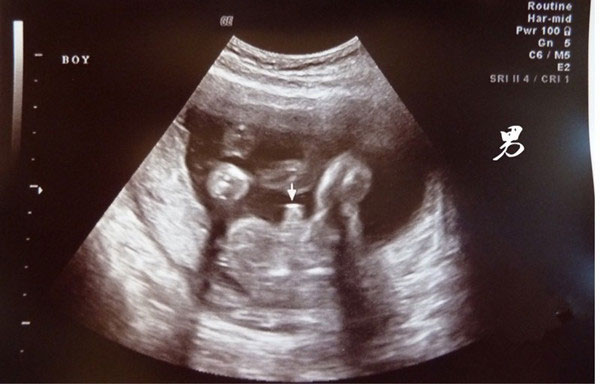

b超有这两点基本是男孩没跑了,具体是哪两点呢?

怀孕之后,腹中宝宝是男孩还是女孩一直以来都是大家所好奇的事情。在怀孕期间,特别是孕妈都会格外注意自己身体上的一些变化和症状,就现在网上非常流行通过孕期症状鉴别男..

b超对胎儿有影响吗-明白这两点让你远离b超误区

b超对胎儿有影响吗?怀孕期间,孕妈妈们要做许许多多的检查,而b超就是其中之一。孕妈妈在怀孕期间,医生会安排三次B超检查,分别为孕早期、孕中期、孕晚期,根据胎儿发育..